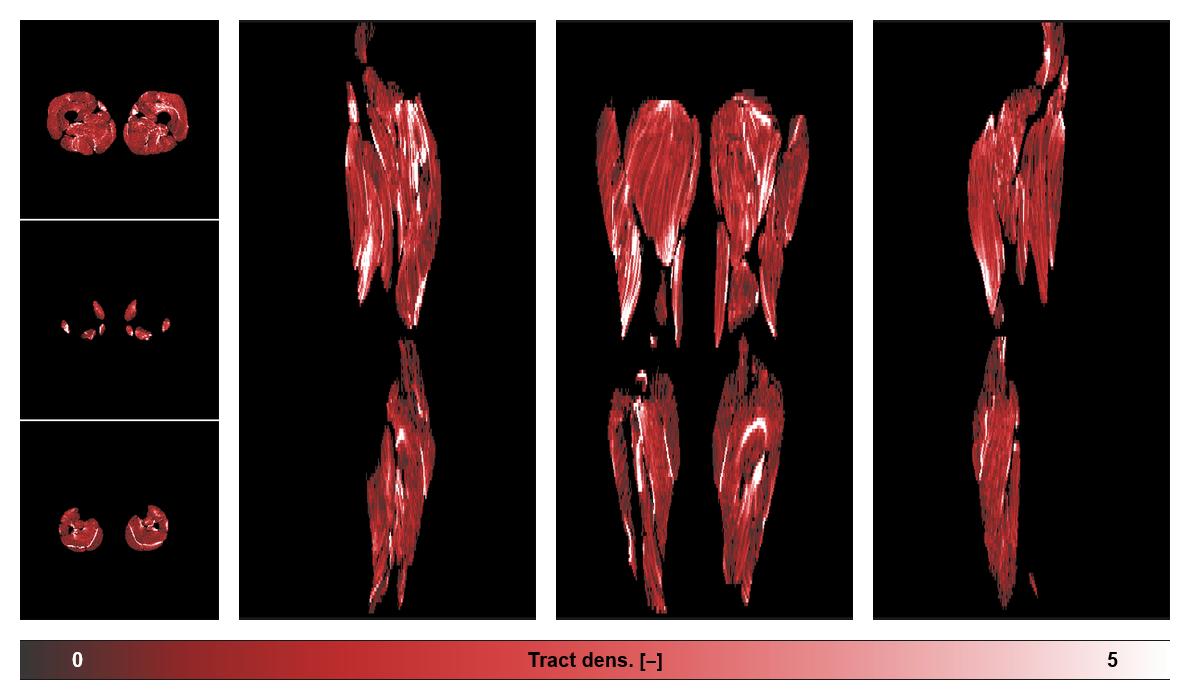

• Muscle fiber density map

Muscle fiber tract density map based on whole leg DTI based fiber tractography.